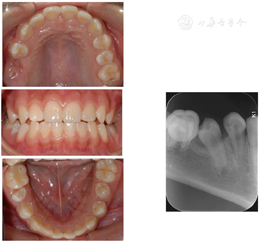

囊肿完全愈合;45和15萌出;17萌出并近中移动至16位置。

第一恒磨牙严重龋坏或缺失后前移第二、三恒磨牙替代修复治疗,减少了患者缺失牙痛苦,也避免了修复带来的各种缺点。根据研究显示:在第二恒磨牙未萌出时即拔除第一恒磨牙可使第二恒磨牙在萌出过程中自动向第一恒磨牙的位置调整,这可使部分牙无需矫治或大大缩短矫治疗程[5]。本例中,阻生的恒牙为年轻恒牙,牙根发育未完成,仍有一定的自行萌出潜力[6]。在拔除16残根后,利用产生的间隙,阻生的15自行萌出,且17近中移动,与15之间的间隙基本关闭,达到了较好的临床治疗效果。后续需继续观察随访18发育及萌出情况。